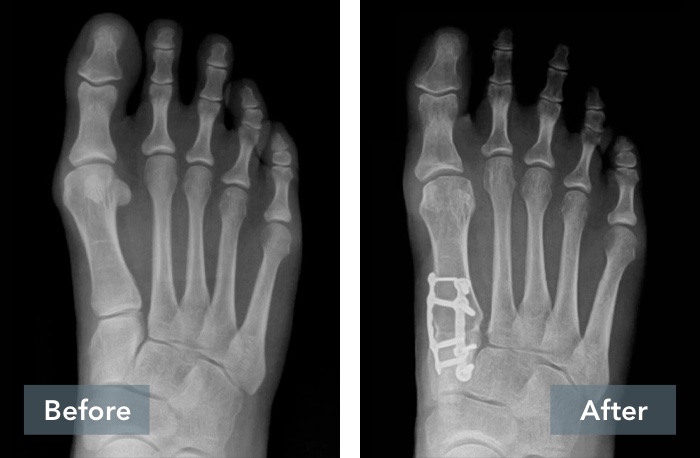

See the Results

Lapiplasty® Before & After Results

A common misconception is that a bunion is simply a “bump” that can be “shaved off.” But, bunions are more than a bump – they are complex 3D problems caused by an unstable joint in the middle of the foot. While the majority of bunion surgery is only 2D and fails to address the root cause, Lapiplasty® provides a 3D correction and secures the unstable joint.

While traditional 2D osteotomy surgery merely cuts & shifts the bone to address the cosmetic bump, Lapiplasty® 3D Bunion Correction™ does more — it corrects the entire bone in 3D and secures the unstable foundation to get you back on your feet quickly in a walking boot. The Lapiplasty® Procedure has also shown low recurrence; 97% and 99% maintain 3D correction in 13 and 17 months respectively.1,3